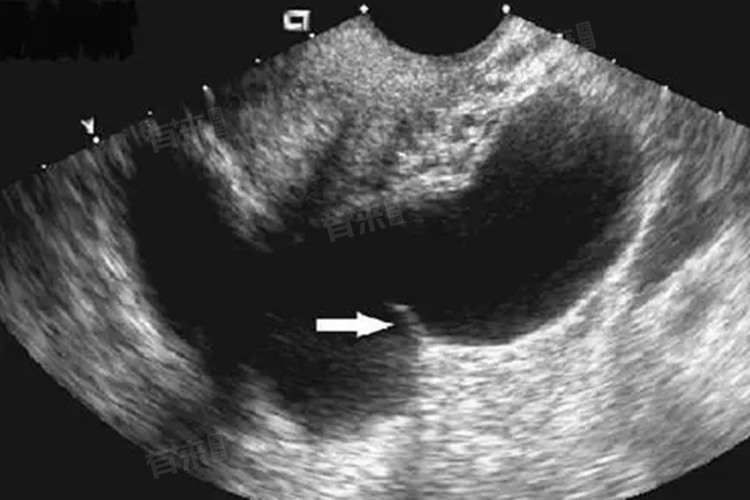

需要注意,并不是所有患有输卵管囊肿的女性都会经历上述所有症状,有的甚至完全无症状。因此,定期进行妇科检查非常重要,特别是对于有生育需求的女性来说更是如此。如果怀疑自己可能患有输卵管囊肿或者出现了相关症状,应及时就医咨询专业医生,通过适当的诊断手段(如超声波检查)来确认情况并获得相应的治疗建议。